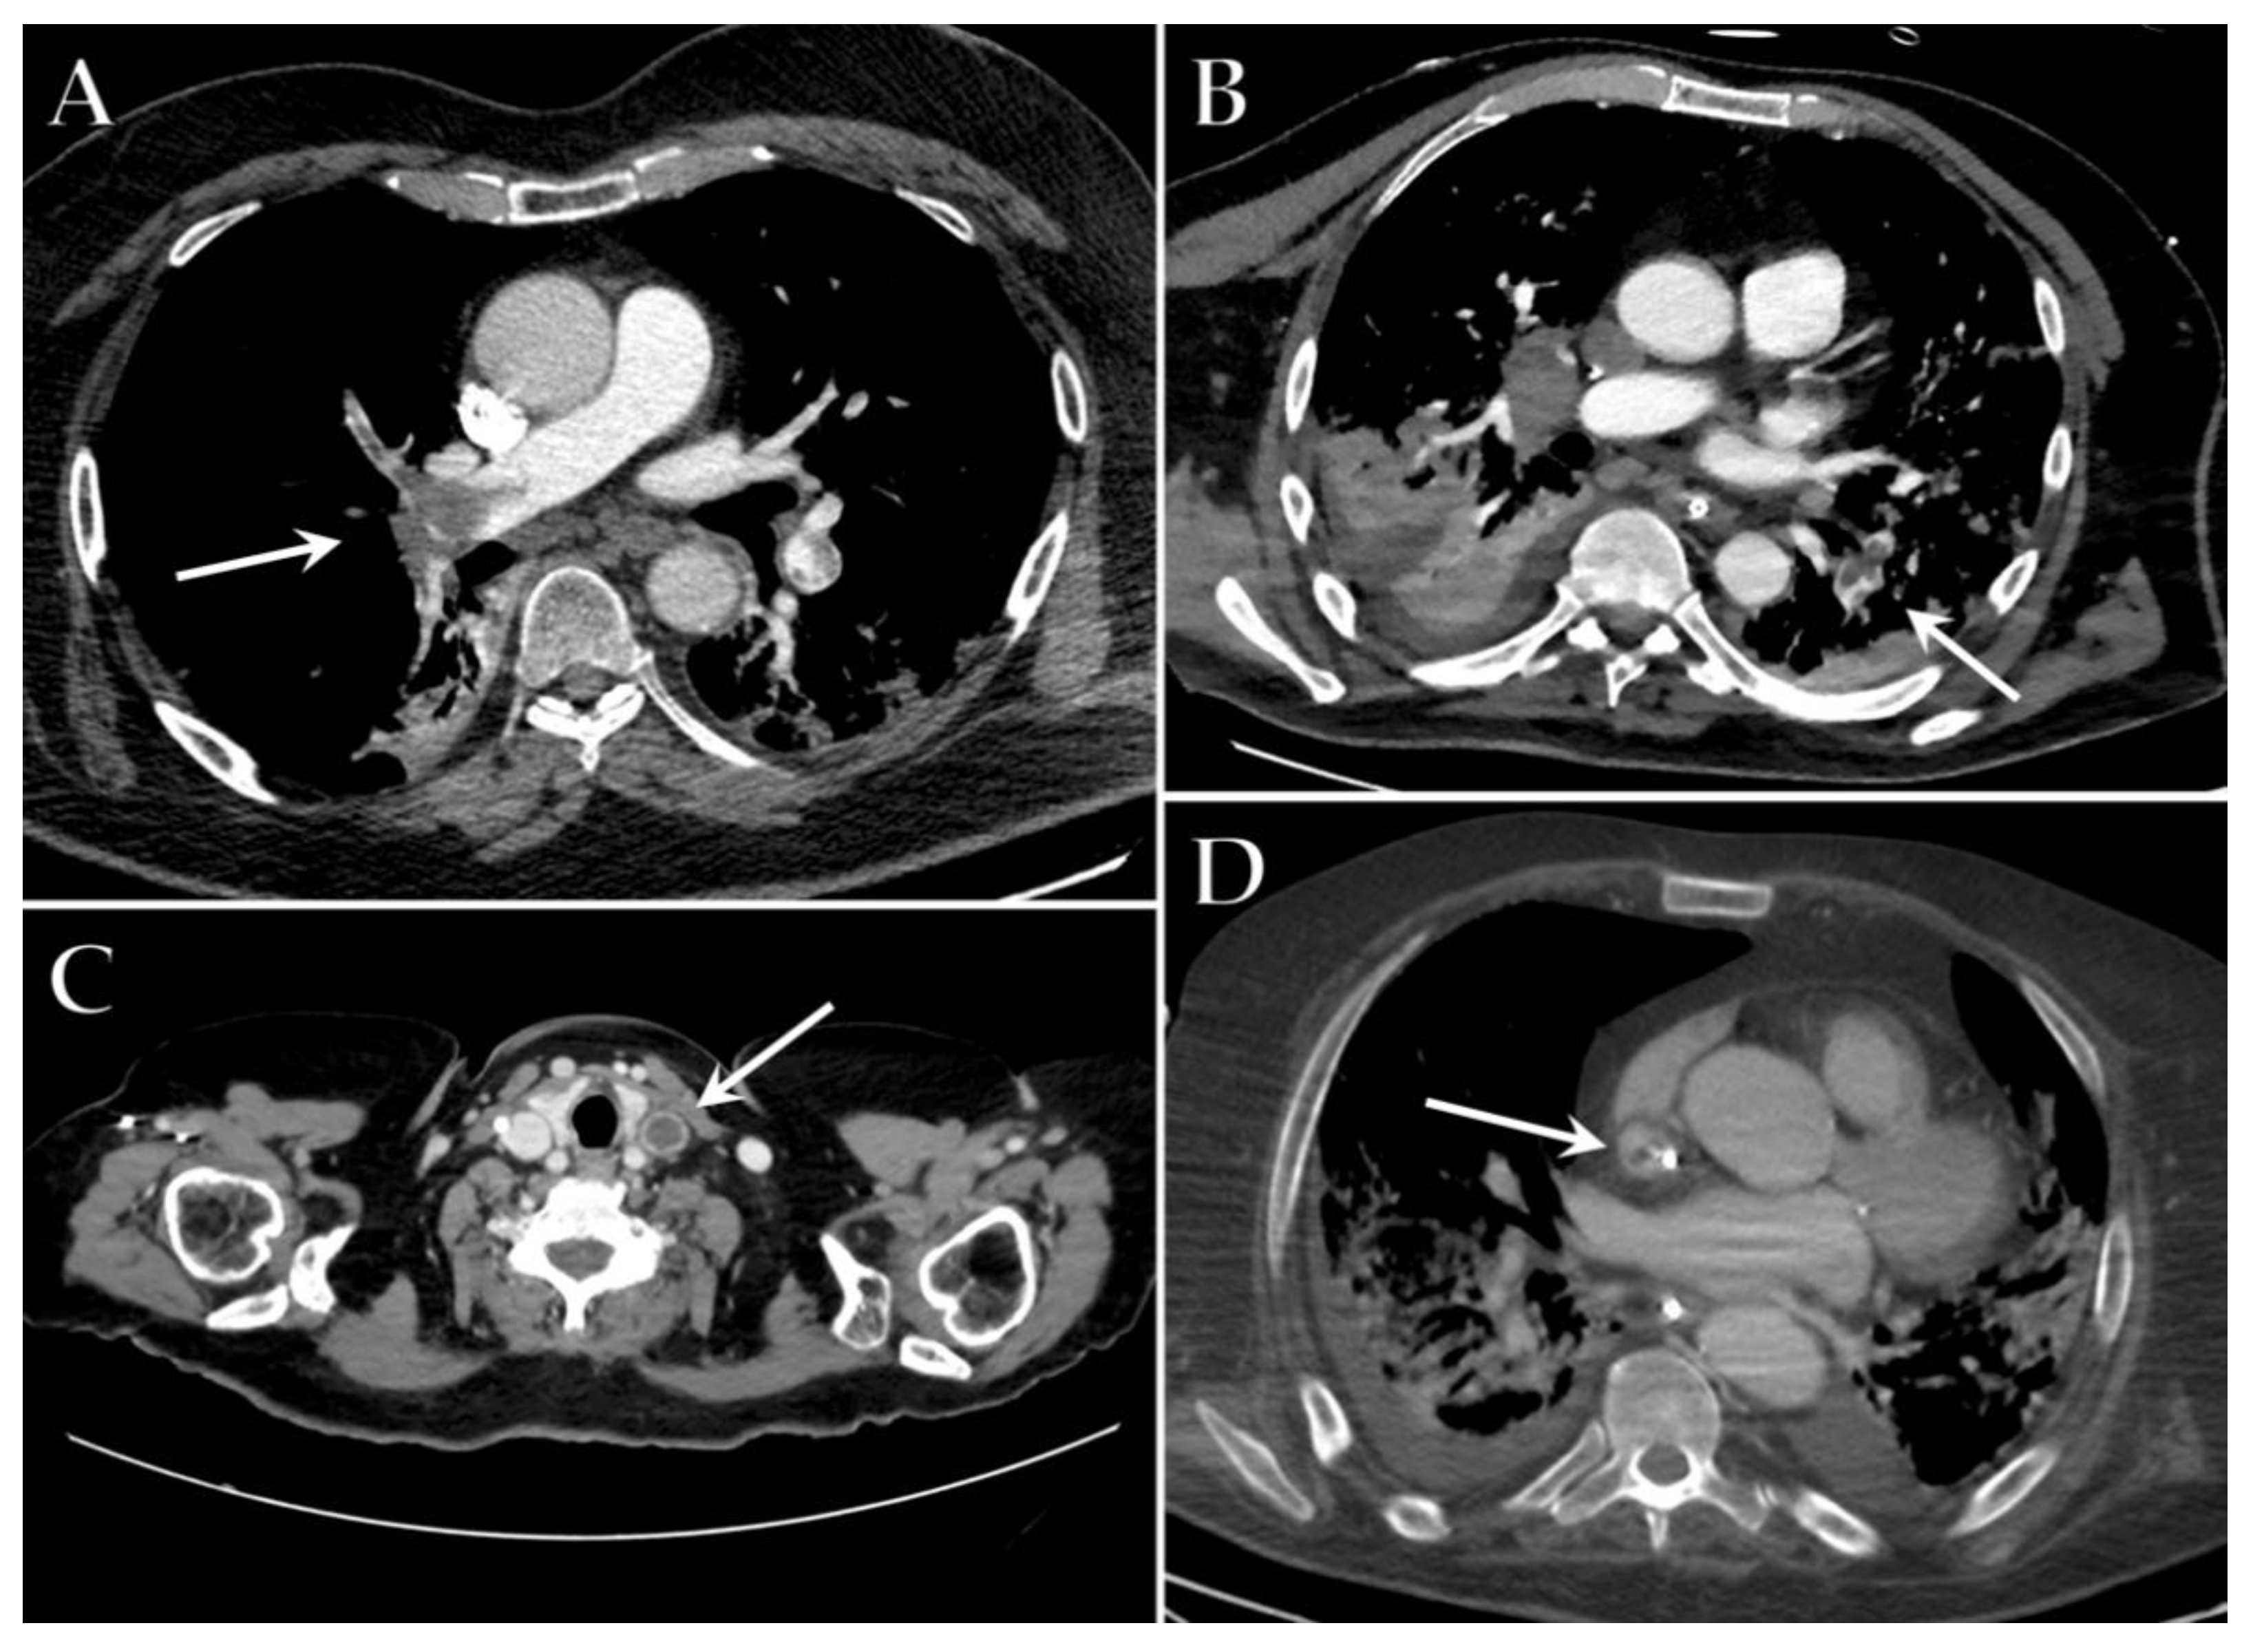

6. Vascular Complications